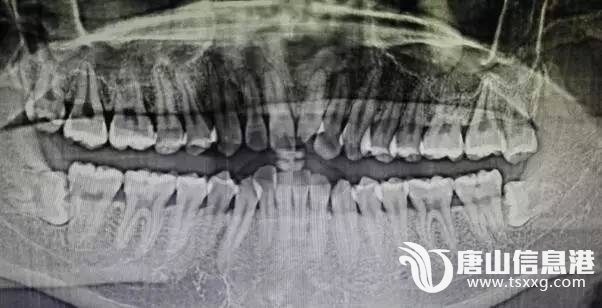

(张某受伤的部位)华北理工大学学生张某在阳光100健身连锁健身期间,因健身房跑步机调试致张某摔倒,并导致一颗门牙断裂,一颗门牙隐裂,嘴唇撕裂,身体多处摔伤,后健身房无人处理,张某自行去医院治疗。3月15日

(张某医院诊断结果)张某从健身房要到保险公司电话,通过跟保险公司沟通,保险公司回话:①保险公司与健身房保险合同上已写明牙齿属于整容范畴,不在保险范围内;②被保人是健身房,与张某无关,需张某自行与健身房协商理赔事宜。6月20日张某与健身房总经理阮某电话沟通,并将保险公司告知阮某后,在与其协商期间,阮某辱骂张某,后张某等人去健身房与阮某理论,阮某扬言要找社会上人弄张某。